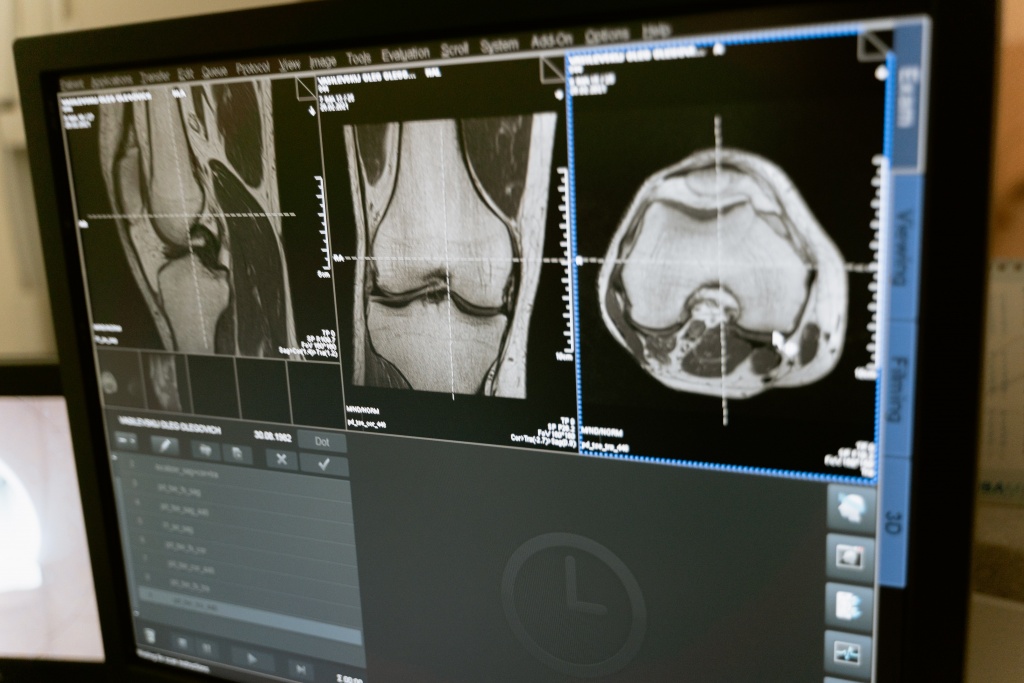

Чтобы установить истинную причину возникновения суставной боли необходимо изучить анамнез пациента и выяснить, не связаны ли они с травмой, инфекцией, погрешностями в питании, гормональными сбоями. При визуальном обследовании изучаются внешнее состояние сустава, кожных покровов, определяется выраженность и характер боли. Затем доктор назначит общее и биохимическое исследование крови, чтобы определить наличие или отсутствие воспалительного процесса, патологических изменений. Далее проводится рентгенограмма суставов, которая поможет в том числе определить изменение рельефа поверхности сустава, наличие подвывихов, остеопороза, краевых костных разрастаний или дефектов, изменения высоты суставной щели. К неинвазивным методам исследования относится и денситометрия — определение (с помощью УЗИ, МРТ и КТ) плотности костной и хрящевой ткани.